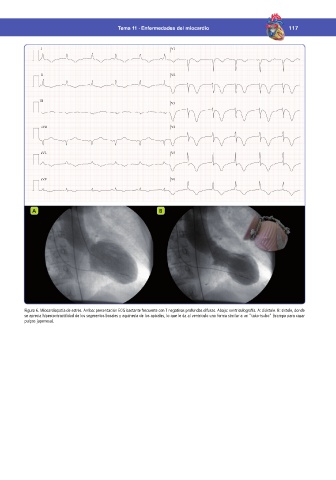

Figura 6. Miocardiopatía de estrés. Arriba: presentación ECG bastante frecuente con T negativas profundas difusas. Abajo: ventriculografía. A: diástole. B: sístole, donde

se aprecia hipercontractilidad de los segmentos basales y aquinesia de los apicales, lo que le da al ventrículo una forma similar a un “tako-tsubo” (trampa para cazar

pulpos japonesa).